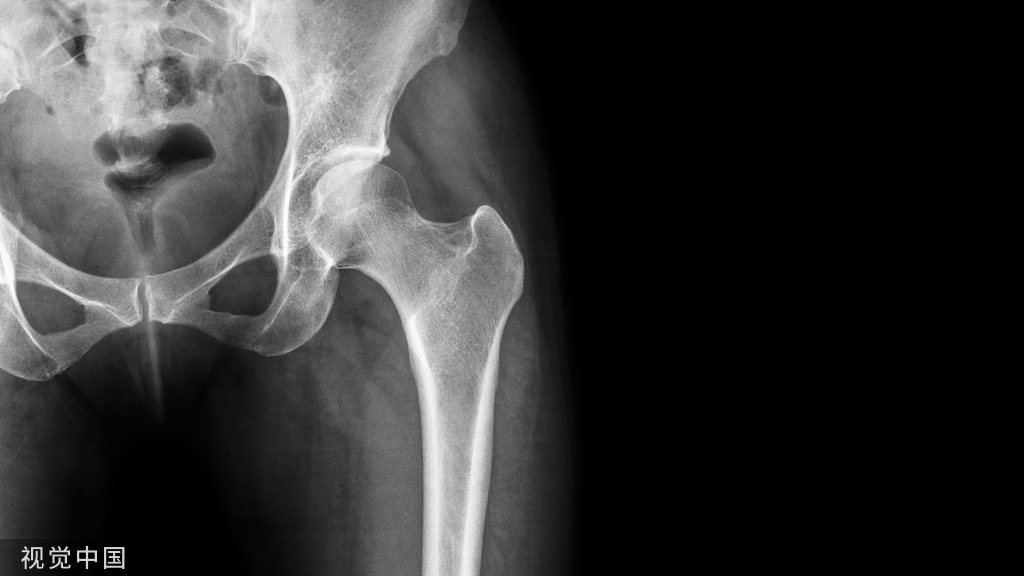

髋关节镜是什么手术?

髋关节镜技术是使用关节镜器械进行检查和手术的微创技术,关节镜既是一种微创检查手段,能够“眼见为实”的看到损伤,确定损伤部位和损伤程度,同时关节镜器械可以直达病损部位,实施微创手术修复。